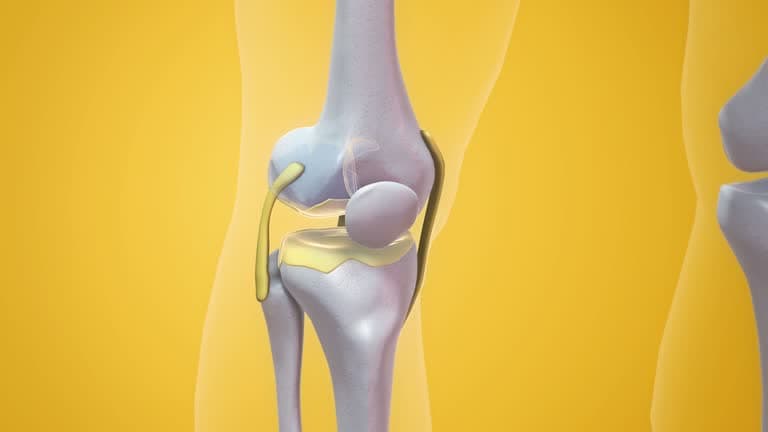

Stiffness in the knee and immobility that persist despite conservative treatments are significant indicators that you might need a knee replacement. Chronic stiffness can severely restrict your range of motion, making it difficult to perform everyday activities such as walking, standing, or bending your knee. This limitation often results from advanced arthritis or significant joint damage, where the cartilage has worn down, causing the bones to rub against each other. If physical therapy, medications, and other non-surgical treatments fail to improve the stiffness and you find that your mobility continues to deteriorate, it may be time to consider knee replacement surgery. This procedure can relieve pain, restore function, and significantly improve your quality of life, allowing you to return to a more active and comfortable lifestyle.

Bowing of the leg, or the appearance of your leg curving inward or outward, can be a strong indicator that you may need a knee replacement. This condition often results from severe wear and tear on the knee joint due to advanced arthritis, where the cartilage that cushions the bones has significantly degraded. This degradation leads to bone-on-bone contact, causing the leg to bow as the joint becomes misaligned. The bowing not only alters the leg's appearance but also affects your overall gait and posture, leading to further discomfort and pain. If conservative treatments like bracing, physical therapy, or medications fail to correct the misalignment or alleviate the pain, knee replacement surgery may be necessary to restore proper joint function and alignment. By addressing the root cause of the bowing, knee replacement can help you regain mobility, reduce pain, and improve your quality of life.

Noticeable changes in the appearance of your knee can be a significant indicator that you might need a knee replacement. These changes can include visible deformities, such as bowing or a pronounced inward or outward curve, swelling that doesn't subside, or a misshapen knee due to joint damage or bone deterioration. These physical alterations often result from conditions like advanced arthritis or severe joint degeneration, where the cartilage that cushions the joint has worn away, leading to bone-on-bone contact and causing the knee to change shape. If these changes in appearance are accompanied by persistent pain, stiffness, and reduced mobility, and if conservative treatments like medications or physical therapy no longer provide relief, it may be time to consider knee replacement surgery. This procedure can help restore the knee's function and appearance, alleviate pain, and improve your overall quality of life.